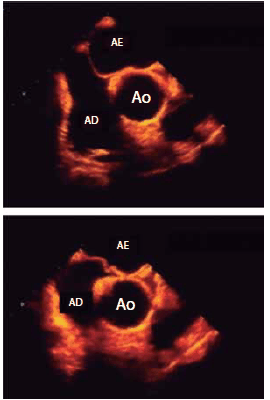

Assinale a alternativa que apresenta corretamente uma causa para a ampla mobilidade ao longo do ciclo cardíaco da estrutura entre o átrio esquerdo (AE) e o átrio direito (AD) observada a seguir.

(Arquivo pessoal; imagem usada com autorização)